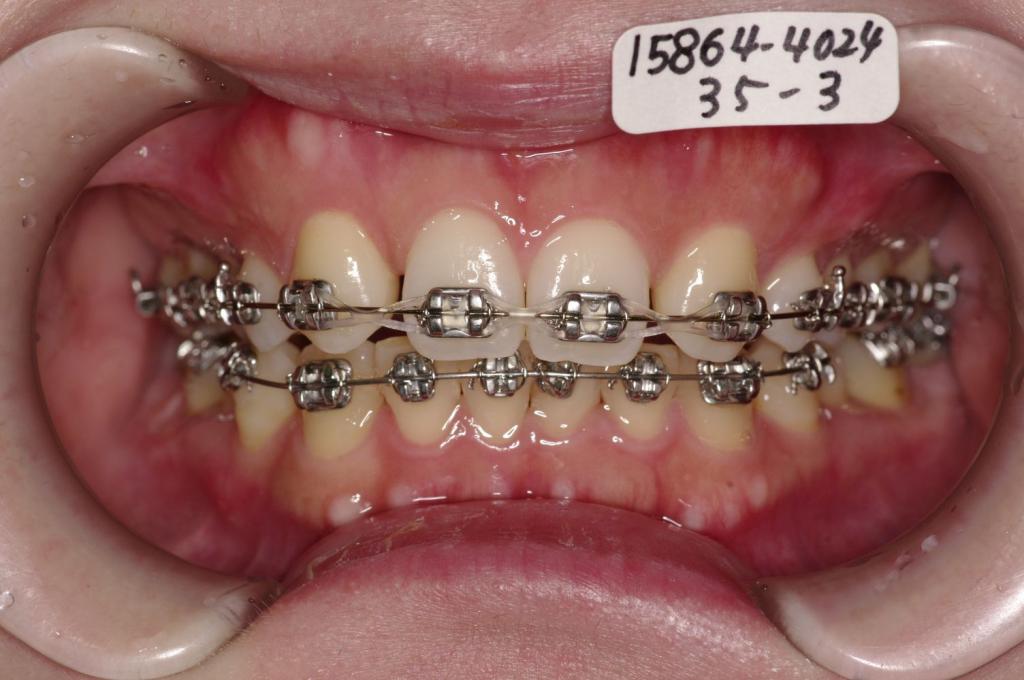

装置の種類及び治療法 診断:両側上顎側切歯先天欠如 叢生

治療方法および装置:マルチブラケット装置

High pull J-hook headgear

抜歯:右上 /左上

右下85 /左下58

欠損歯:右上82 /左上28

右下 /左下

治療期間:23ヶ月

治療前

歯欠損の矯正治療前口内写真NO.147